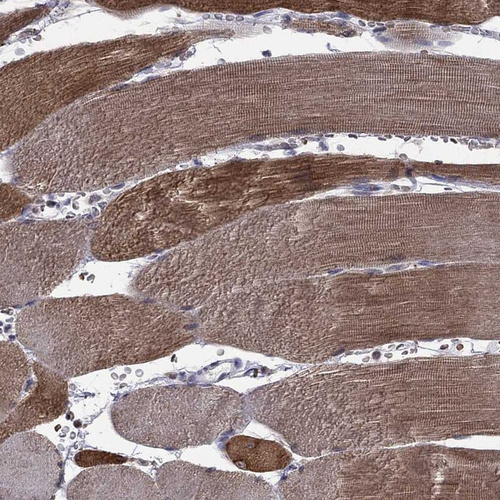

Immunohistochemical staining of human heart muscle shows strong cytoplasmic positivity in cardiomyocytes.